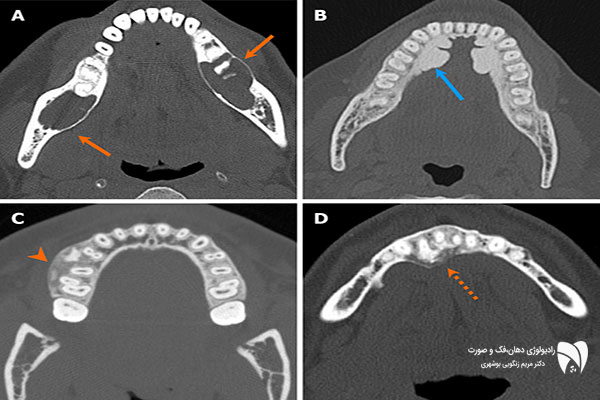

التصوير المقطعي المحوسب لفحص آفات الأسنان

التصوير المقطعي المحوسب المخروطي (CBCT) هو تقنية تصوير بالأشعة السينية تُستخدم لفحص آفات الفم، حيث تُوفر صورًا ثلاثية الأبعاد للأسنان والفكين والأنسجة الرخوة المحيطة. تُساعد هذه التقنية أطباء الأسنان على تشخيص مشاكل الفم والفكين المعقدة (مثل الالتهابات والأورام والأكياس) بدقة عالية، وتخطيط علاج دقيق.